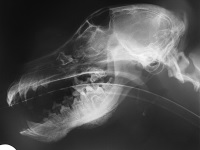

On the lateral radiograph it is also evident that the first maxillary molar has been displaced

dorsally. On the dorso-ventral view this tooth is displaced medio-rostrally. Intra-oral

radiographs (or computed tomography scan) at various angles are advocated to ascertain the 3

dimensional position of this tooth. Once this has been determined appropriate therapy

(surgical extraction?) can be planned.